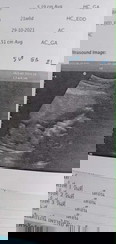

เด็ก21Week แม่ๆเห็นเพศน้อนกันรึยังเอ่ยเราตื่นเต้นมากเรยค่ะ

บ้านนี้ผช.70%คุมหมอบอก

บ้านนี้เห็นตอน20วีค แค่60%เองค่ะ